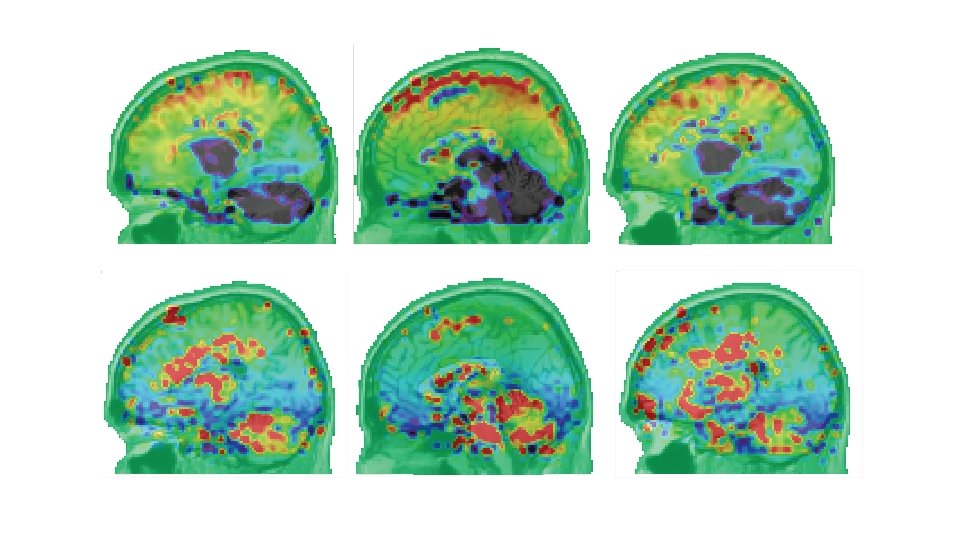

Figura 6. 4. Estructura de retrasos para el hilo principal μ± 3σ (en segundos)Tramo “Pico”. Las flechas indican algunos sitios de interés a modo de ejemplo como corteza auditiva, tálamo, cerebelo.

Figura 6. 5. Estructura de retrasos para el hilo principal μ± 3σ - Tramo “Onda”. Las flechas indican tálamo y ganglios de la base.